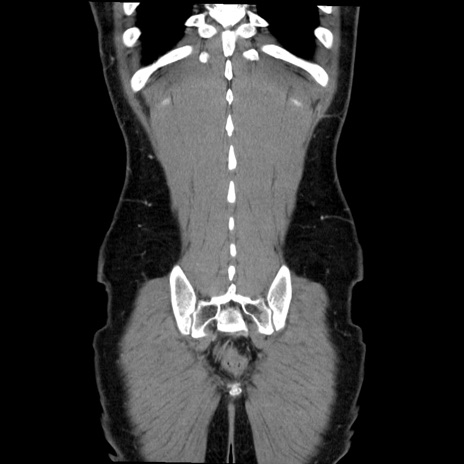

症例36(冠状断像)

【症例】20歳代 男性

【主訴】心窩部痛

【現病歴】今朝より上腹部痛あり。一旦軽快していたが再度出現したため救急要請。昨日夕に白身の魚を含む刺身を食べた。

【身体所見】BP 136/89mmHg、HR 74/min、BT 37.0℃、腹部:膨満、軟、心窩部に圧痛あり。反跳痛なし、筋性防御なし、腸雑音やや亢進あり。

【データ】WBC 17700、CRP 0.48